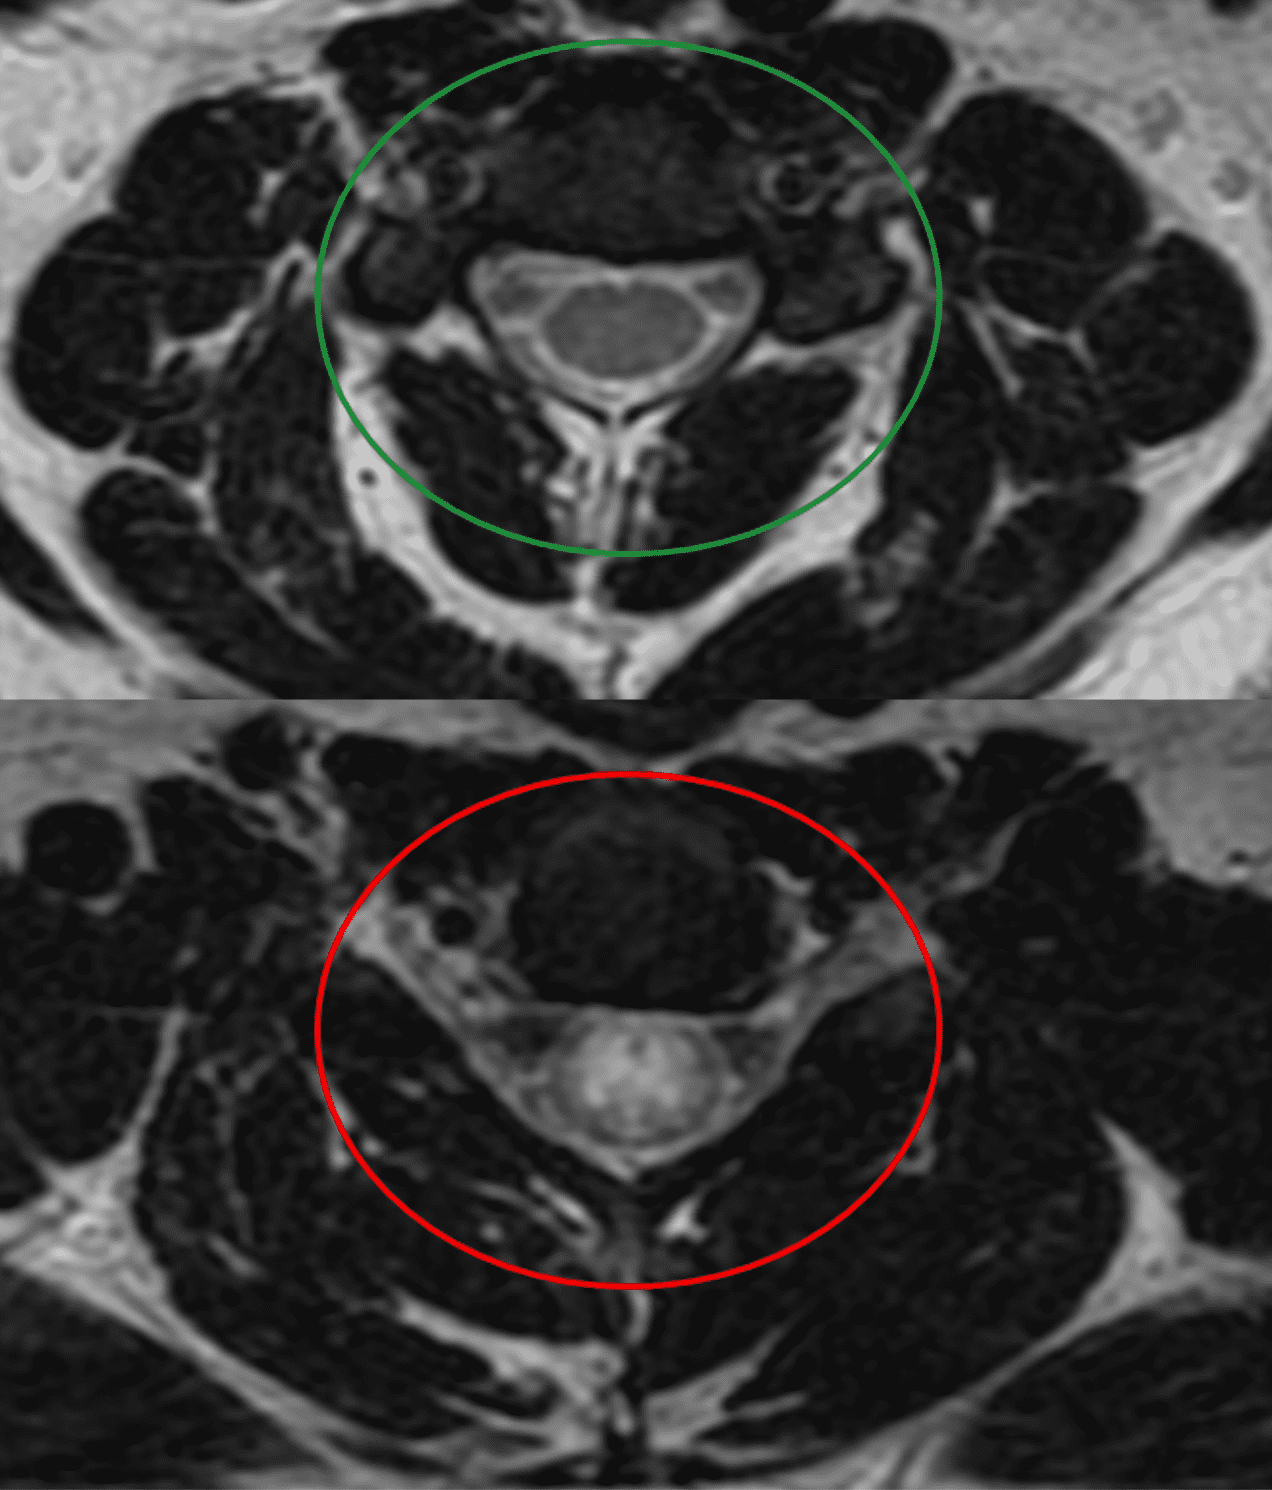

Joseph, a fellowship trained, board certified orthopedic surgeon. Joseph Spine is an advanced center for spine, scoliosis and minimally invasive surgery. CT scans produce excellent detail used to diagnose osteoarthritis and fractures. People with metallic implants may not be able to undergo an MRI because of the strong magnetic field used in the test.Ī CT scan is better than an MRI for imaging calcified tissues, like bones. MRIs may also be used in cases where the X-rays are contraindicated, such as with pregnant women. An MRI can be better at detecting abnormalities of the spinal cord, bulging discs, small disc herniation’s, pinched nerves and other soft tissue problems. MRI scans are better for imaging water-containing tissue.

What the difference between an MRI and a CT SCAN?Īn MRI differs from a CAT scan (also called a CT scan or a computed axial tomography scan) because it does not use radiation. Imaging patients with metal (no magnet).Evaluating lung and chest issues (see lung scan image to the right).Pinpointing issues with bony structures (injuries).Imaging bone, soft tissue and blood vessels at the same time.The cross-sectional images generated during a CT scan can be reformatted in multiple planes, and can also generate three-dimensional images. Using CT, the bony structure of the spine vertebrae is clearly and accurately shown, as are intervertebral disks and, to some degree, the spinal cord soft tissues. CT images of internal organs, bones, soft tissue and blood vessels provide greater detail than traditional x-rays, particularly of soft tissues and blood vessels. Showing tissue difference between normal and abnormalĬomputed tomography, more commonly known as a CT or CAT scan, is a diagnostic medical test that, like traditional x-rays, produces multiple images or pictures of the inside of the body.ĬT scan is a rapid, 5-20 minute painless exam that combines the power of X-rays with computers to produce 360 degrees, cross-sectional views of your body.Imaging organs, soft tissue internal structures (see spine scan image to the right).It can give a very clear picture of the structure of the spine. The machine also makes a banging noise while it is working, which can make patients uncomfortable. Patients who are afraid this might happen should talk to the doctor beforehand, who may give them some medication to help them relax. There is a small theoretical risk to the fetus in the first 12 weeks of pregnancy, and therefore scans are not performed on pregnant women during this time.īecause patients have to lie inside a large cylinder while the scans are being made some people get claustrophobic during the test. Since radiation is not used, the procedure can be repeated without problems. The test is not painful you cannot feel it. There are no known dangers or side effects connected to an MRI scan. MRI also may show problems that cannot be seen with other imaging methods. In many cases, MRI gives different information about structures in the body that can be seen with computed tomography (CT) scan. Magnetic resonance imaging (MRI) is a test that uses a magnetic field and pulses of radio wave energy to make pictures of organs and structures inside the body. In actuality, both tests are valuable diagnostic tools that should be utilized by your spine care physician. They also wonder if one test is better than the other. Patients often inquire about the differences between an MRI scan and a CT scan.